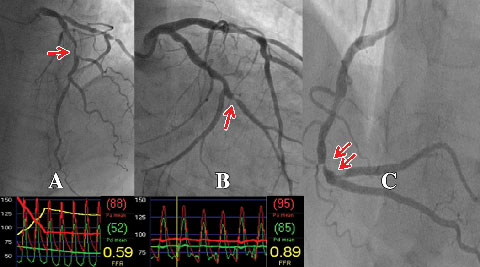

An important recent advance has been the ability to accurately determine the physiological significance of an individual coronary lesion by measuring FFR.7,15 FFR is defined as the ratio between coronary pressure distal to the stenosis in question and aortic pressure measured simultaneously during adenosine-induced hyperaemia. Coronary pressure is obtained by passing a pressure guide wire distal to the coronary stenosis in a manner analogous to passing a guide wire for the purpose of PCI.7,15 As such, it can be easily and safely performed by those experienced in performing PCI. If PCI is indicated as a result of the FFR measurement, the coronary pressure wire can be used for stent delivery. In the case of multiple lesions in one or more vessels, each individual lesion can be examined by the pressure wire (Box 2). In this way, the lesion or lesions causing ischaemia can be determined in a more precise manner than the traditional method of correlating the angiographic findings with the results of stress testing, or by using angiographic criteria alone.

A wealth of data has validated the accuracy of FFR as a measure of myocardial ischaemia.7,15,19 An FFR value of ≤ 0.80 identifies ischaemia-causing coronary stenoses with an accuracy of greater than 90%. An FFR > 0.80 excludes ischaemia with a predictive accuracy of 95%.15